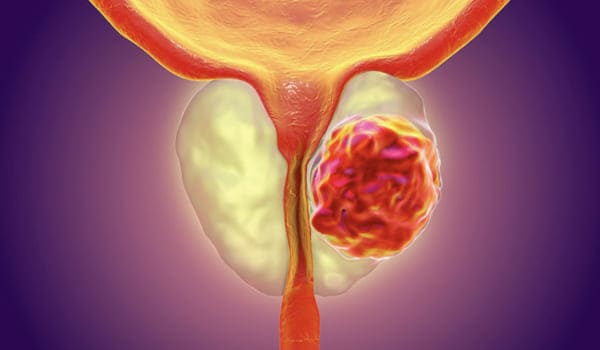

Es un Tumor maligno que aparece en la glándula prostática. En el mundo es el tumor maligno más frecuente en hombres.

Ante la anormalidad en cualquiera de las dos pruebas, se determina una sospecha de cáncer de próstata, por lo que se debe realizar una confirmación por medio de una biopsia de próstata.

En fases avanzadas puede producir dolor óseo principalmente columna y cadera, orina con sangre, pérdida de fuerza en miembros inferiores entre otros.

Es importante recalcar que la cirugía próstata para la Hiperplasia Prostática Benigna (HPB) es una cirugía en la cual se retira la porción de la próstata que obstruye para orinar únicamente. En la cirugía de cáncer de próstata se remueve la totalidad de la próstata por lo cual es esperado que se presenten mayores riesgos para la salud del paciente.